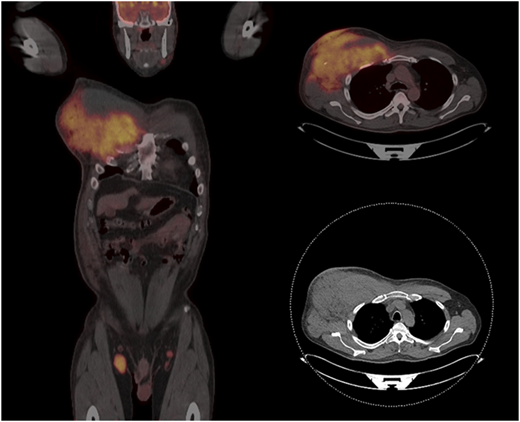

The best initial treatment depends on the prior therapy for the underlying indolent lymphoma and the histology at the time of transformation (Figure 3). There are several clinical scenarios to consider: tFL in treatment-naïve patients with FL (including simultaneous diagnosis of FL/tFL), tFL after prior anthracycline-based chemoimmunotherapy, and tFL developing after prior therapy that did not include cytotoxic chemotherapy. An example of a scenario with almost no data is when HT occurs after prior bendamustine-based chemoimmunotherapy and whether to treat these patients similarly to anthracycline-exposed patients is unclear.

Graphic summary of how I treat tFL. CIT, chemoimmunotherapy; BSC, best supportive care; HCT, hematopoietic stem cell transplant.

Graphic summary of how I treat tFL. CIT, chemoimmunotherapy; BSC, best supportive care; HCT, hematopoietic stem cell transplant.